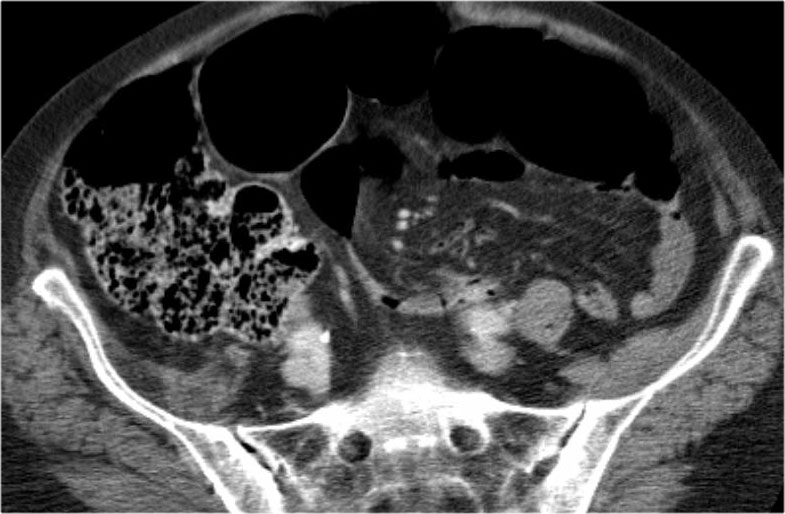

Ca lâm sàng bên trái cho thấy một bệnh nhân khác bị tắc ruột dạng quai kín.

Mặc dù các mạch máu ngấm thuốc tốt, nhưng dường như thành ruột không ngấm thuốc.

Các dấu hiệu thiếu máu cục bộ khác trong ca này bao gồm phù nề mạc treo và dày thành ruột.

Ruột bị nhồi máu được phát hiện trong quá trình phẫu thuật.

Nếu quai kín dài hơn và định hướng vuông góc với mặt phẳng cắt, chúng ta sẽ thấy một cụm quai ruột như trong ca lâm sàng bên trái.

Đôi khi điều này khó nhận biết chỉ trên các lát cắt ngang và các tái tạo mặt phẳng coronal hoặc sagittal có thể hữu ích.

Trong ca này, cũng có phù nề mạc treo và cổ